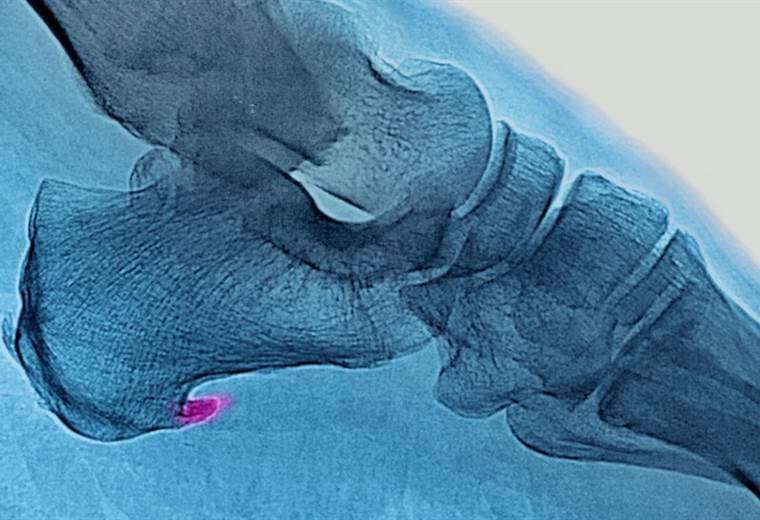

Se trata de un dolor agudo en la planta del pie, justo por delante del talón, que se intensifica cuando nos levantamos o pasamos un período de tiempo sin movernos.

Hablamos de la fascitis plantar, una de las lesiones más comunes que se puede sufrir a la hora de correr pero que suele pasar desapercibida cuando se está llevando a cabo el ejercicio.

Lo que ocurre es que se produce una inflamación de la membrana que recubre la musculatura de la planta del pie y el talón.

La inflamación se produce cuando se trata compensar con los músculos del pie y sus tendones un desbalance que ocurre en el cuerpo.

Eso se debe a que la fascia plantar cumple una función biomecánica al caminar de absorber y devolver la energía que se produce cuando el pie impacta contra el suelo.